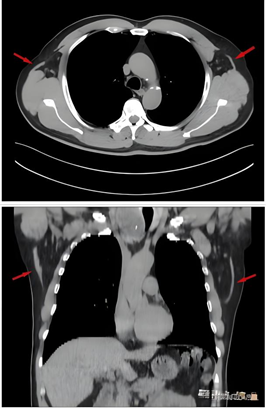

3.贯通:影像衔接,融通临床思维:在学生掌握三维结构后,引入真实的CT平扫影像图,引导学生将3Dbody虚拟仿真数字化教学平台中的理想模型与临床实际影像进行对照,辨识影像中的器官方位、断面,训练其“从立体到平面,再从平面还原立体”的空间思维能力,实现从书本知识到临床应用的平滑转化。